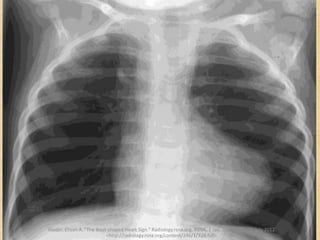

• Frontal chest

radiograph

• The shape of a

wooden boot

• Tetralogy of Fallot

Radiology in Tetralogy of Fallot

• The Boot-shaped

Heart sign

“coeur en sabot”

– The UPPER part of the

Boot: flat / concave

pulmonary trunk

– The TOE--upward

pointing cardiac apex:

concentric right

ventricular

hypertrophy

Accentuated by large lung volume,

small thymus, and lordotic

projection